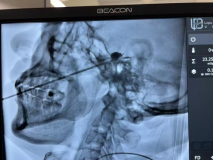

70岁的黄大爷就饱受这种疼痛的折磨。吃饭、简单的触碰,这些日常小事都会引发他剧烈的牙痛,严重影响了他的生活。黄大爷跑了多家医院,最终确诊为三叉神经痛。但他的情况十分棘手,合并肝炎肝硬化失代偿期、慢性肝衰竭、2型糖尿病等多种疾病,凝血功能严重低下,手术治疗的风险极高。抱着最后一线希望,黄大爷来到了北京佑安医院疼痛门诊。罗超副主任医师耐心接诊并严密评估后,认为还有手术治疗的可能。在关雷主任和罗超副主任医师的指导下,团队积极调控黄大爷的凝血功能,制定了详尽的手术计划,为他实施了经皮穿刺三叉神经半月节微球囊压迫术。手术历经1小时顺利完成,黄大爷的疼痛即刻消失,第二天便开心出院,露出了久违的笑容。

面对三叉神经痛,经皮穿刺三叉神经半月节微球囊压迫术是一种有效的治疗方法。这是一种微创介入治疗技术,在患者面部穿刺,导入微小球囊导管至三叉神经节附近,通过短暂压迫阻断疼痛信号传导。它有着诸多优势:仅需局部麻醉,创伤小、恢复快、住院时间短;术后疼痛即刻缓解,有效率超90%;复发率低;适应症广,尤其适合高龄、无法耐受开颅手术的患者;术后并发症少,面部麻木感轻微,大多患者可耐受。适合长期受三叉神经痛困扰且药物治疗效果不佳、无法耐受开颅手术或射频消融治疗、高龄体弱合并其他基础疾病的患者。